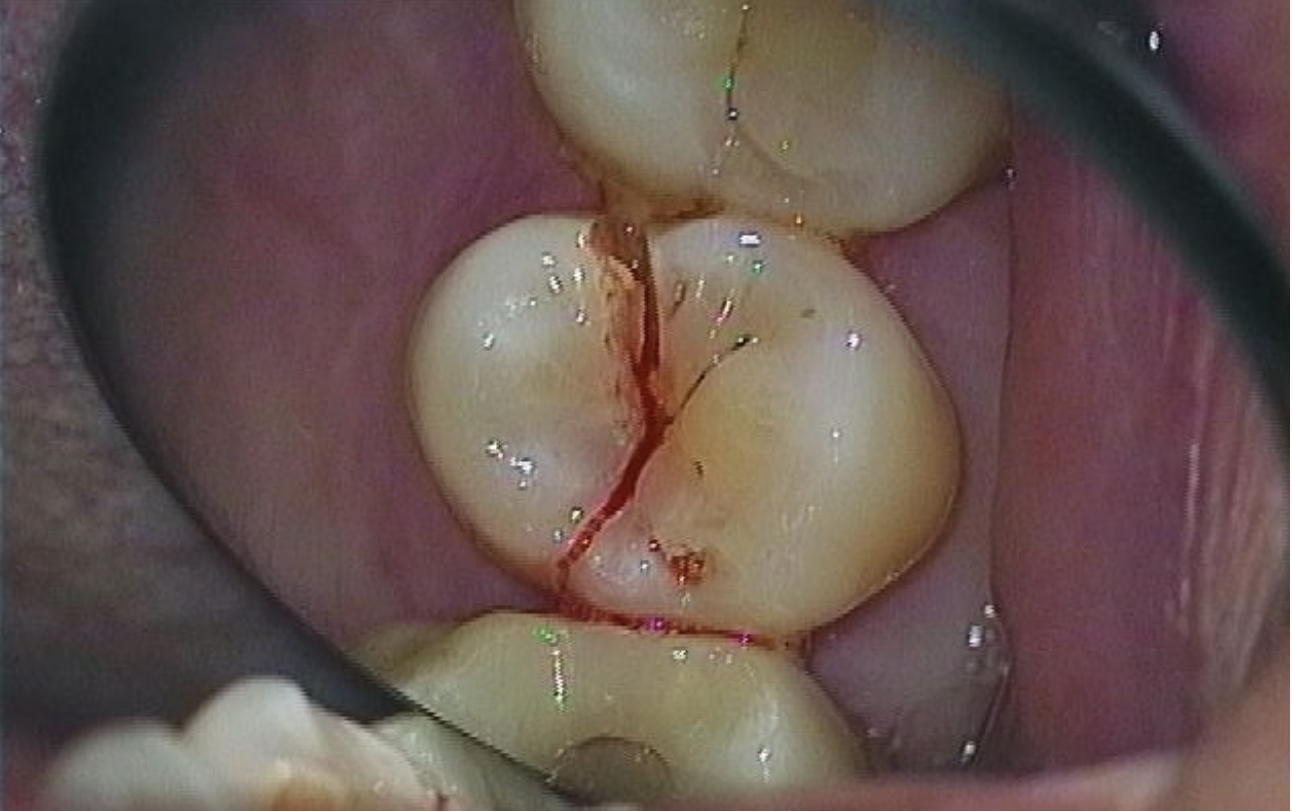

En 54-årig kvinde henvendte sig med en alvorlig fraktur af en lille kindtand i højre side af overkæben. Hun havde ikke tygget i noget specielt hårdt.

Tanden var flækket på langs og kunne ikke bevares.

En nøje undersøgelse med gennemlysning afslørede yderligere 5 tænder med revner. Kun de tre tænder fra overkæben er vist her.

Patienten var startet på antidepressiv medicin for ca. halvandet år siden. Antidepressiv medicin, angstdæmpende medicin og ADHD-medicin øger mængden af signalstoffer i hjernen og virker stimulerende. For ca. 20-30 % resulterer det samtidig i natligt tandpres eller tænderskæren som en skjult bivirkning.

Tand der er flækket på langs på grund af en dyb revne